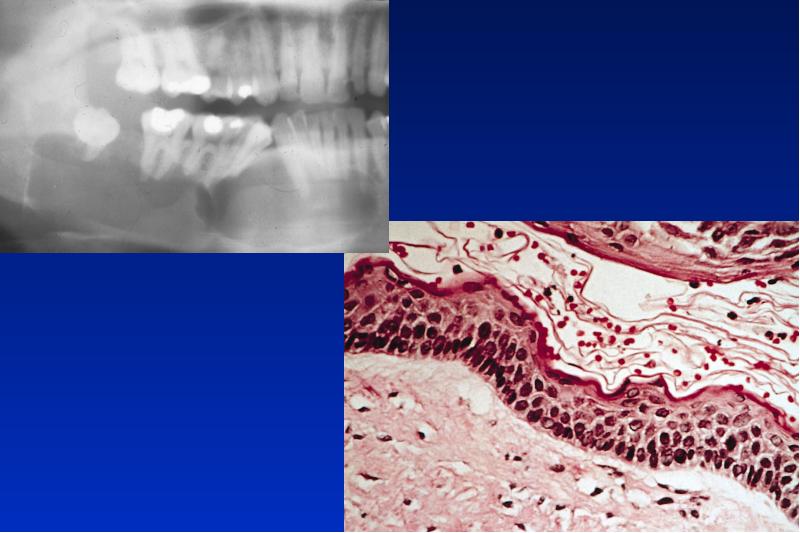

- 23. Gorlin-Goltz Syndrom autosomal dominanter Erbgang Symptome: multiple